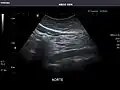

Standard measurement of the abdominal aorta[4]

It can be used on the abdominal aorta to detect or exclude abdominal aortic aneurysm. For this purpose, the standard aortic measurement for abdominal aortic aneurysm is between the outer margins of the aortic wall.[4]

Aorta: Visualized portions normal in caliber, 16 x 15 mm.